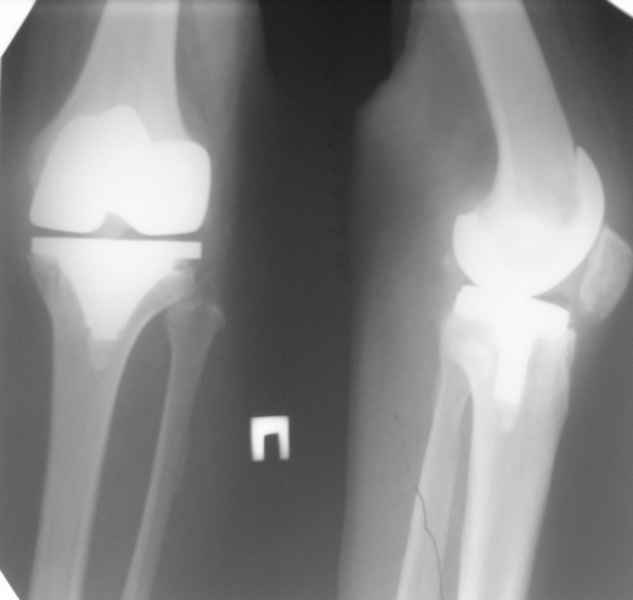

Уважаемые коллеги, Прошу совета. В феврале 2007 года пациентке выполнено эндопротезирование коленного сустава.

13/02/07 |  25/07/07 |  дек. 07 |  25/06/08 |  14/01/09 | Через 1 месяц после операции объем движений 90 градусов, через 2 месяца 60, через 3 - 40, через 5 - качательные движения.

В июле 2007 года выполнена ревизия - полости сустава нет. Капсула сустава имеет толщину от 1 до 1.5 см, собственная связка надколенника имеет толщину до 3 см. Сустав заполнен фиброзно-рубцовой тканью. Компоненты стабильны.

Есть вопросы к установке протеза. Скорее всего тибиальное плато было не конца резецировано и в задненаружных отделах осталась ступенька. Это привело к тому, что тибиальный компонент завалился на варус.